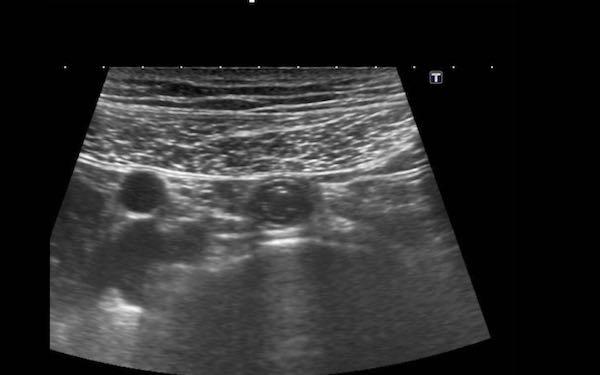

Đây là hình ảnh của hồi tràng tận cùng ở ba trẻ em và người trẻ tuổi khác nhau với các mảng Peyer lớn biểu hiện dưới dạng dày lớp niêm mạc sâu không đối xứng, giảm âm.

Với mỗi kháng nguyên mới, mô bạch huyết lại được tái hoạt hóa.

Ở bệnh nhân trẻ tuổi, cả hạch bạch huyết mạc treo ruột và các mảng Peyer đều lớn hơn nhiều so với người trưởng thành – kể cả về kích thước tuyệt đối.